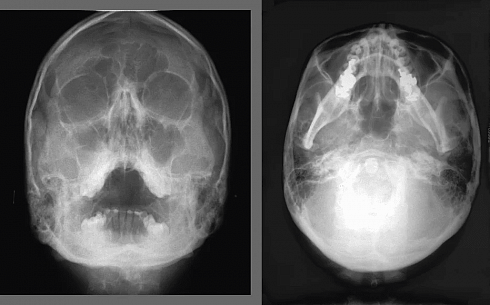

- Основные панорамные и цефалометрические программы (в комплекте): Стандартная панорама взрослого, Стандартная панорама ребенка, — Боковой двойной ВНЧС, Двойной задне-передний ВНЧС, Задне-передний синус (прямой слой), Боковая и передне-задняя цефалометрические проекции, Проекция кисти.